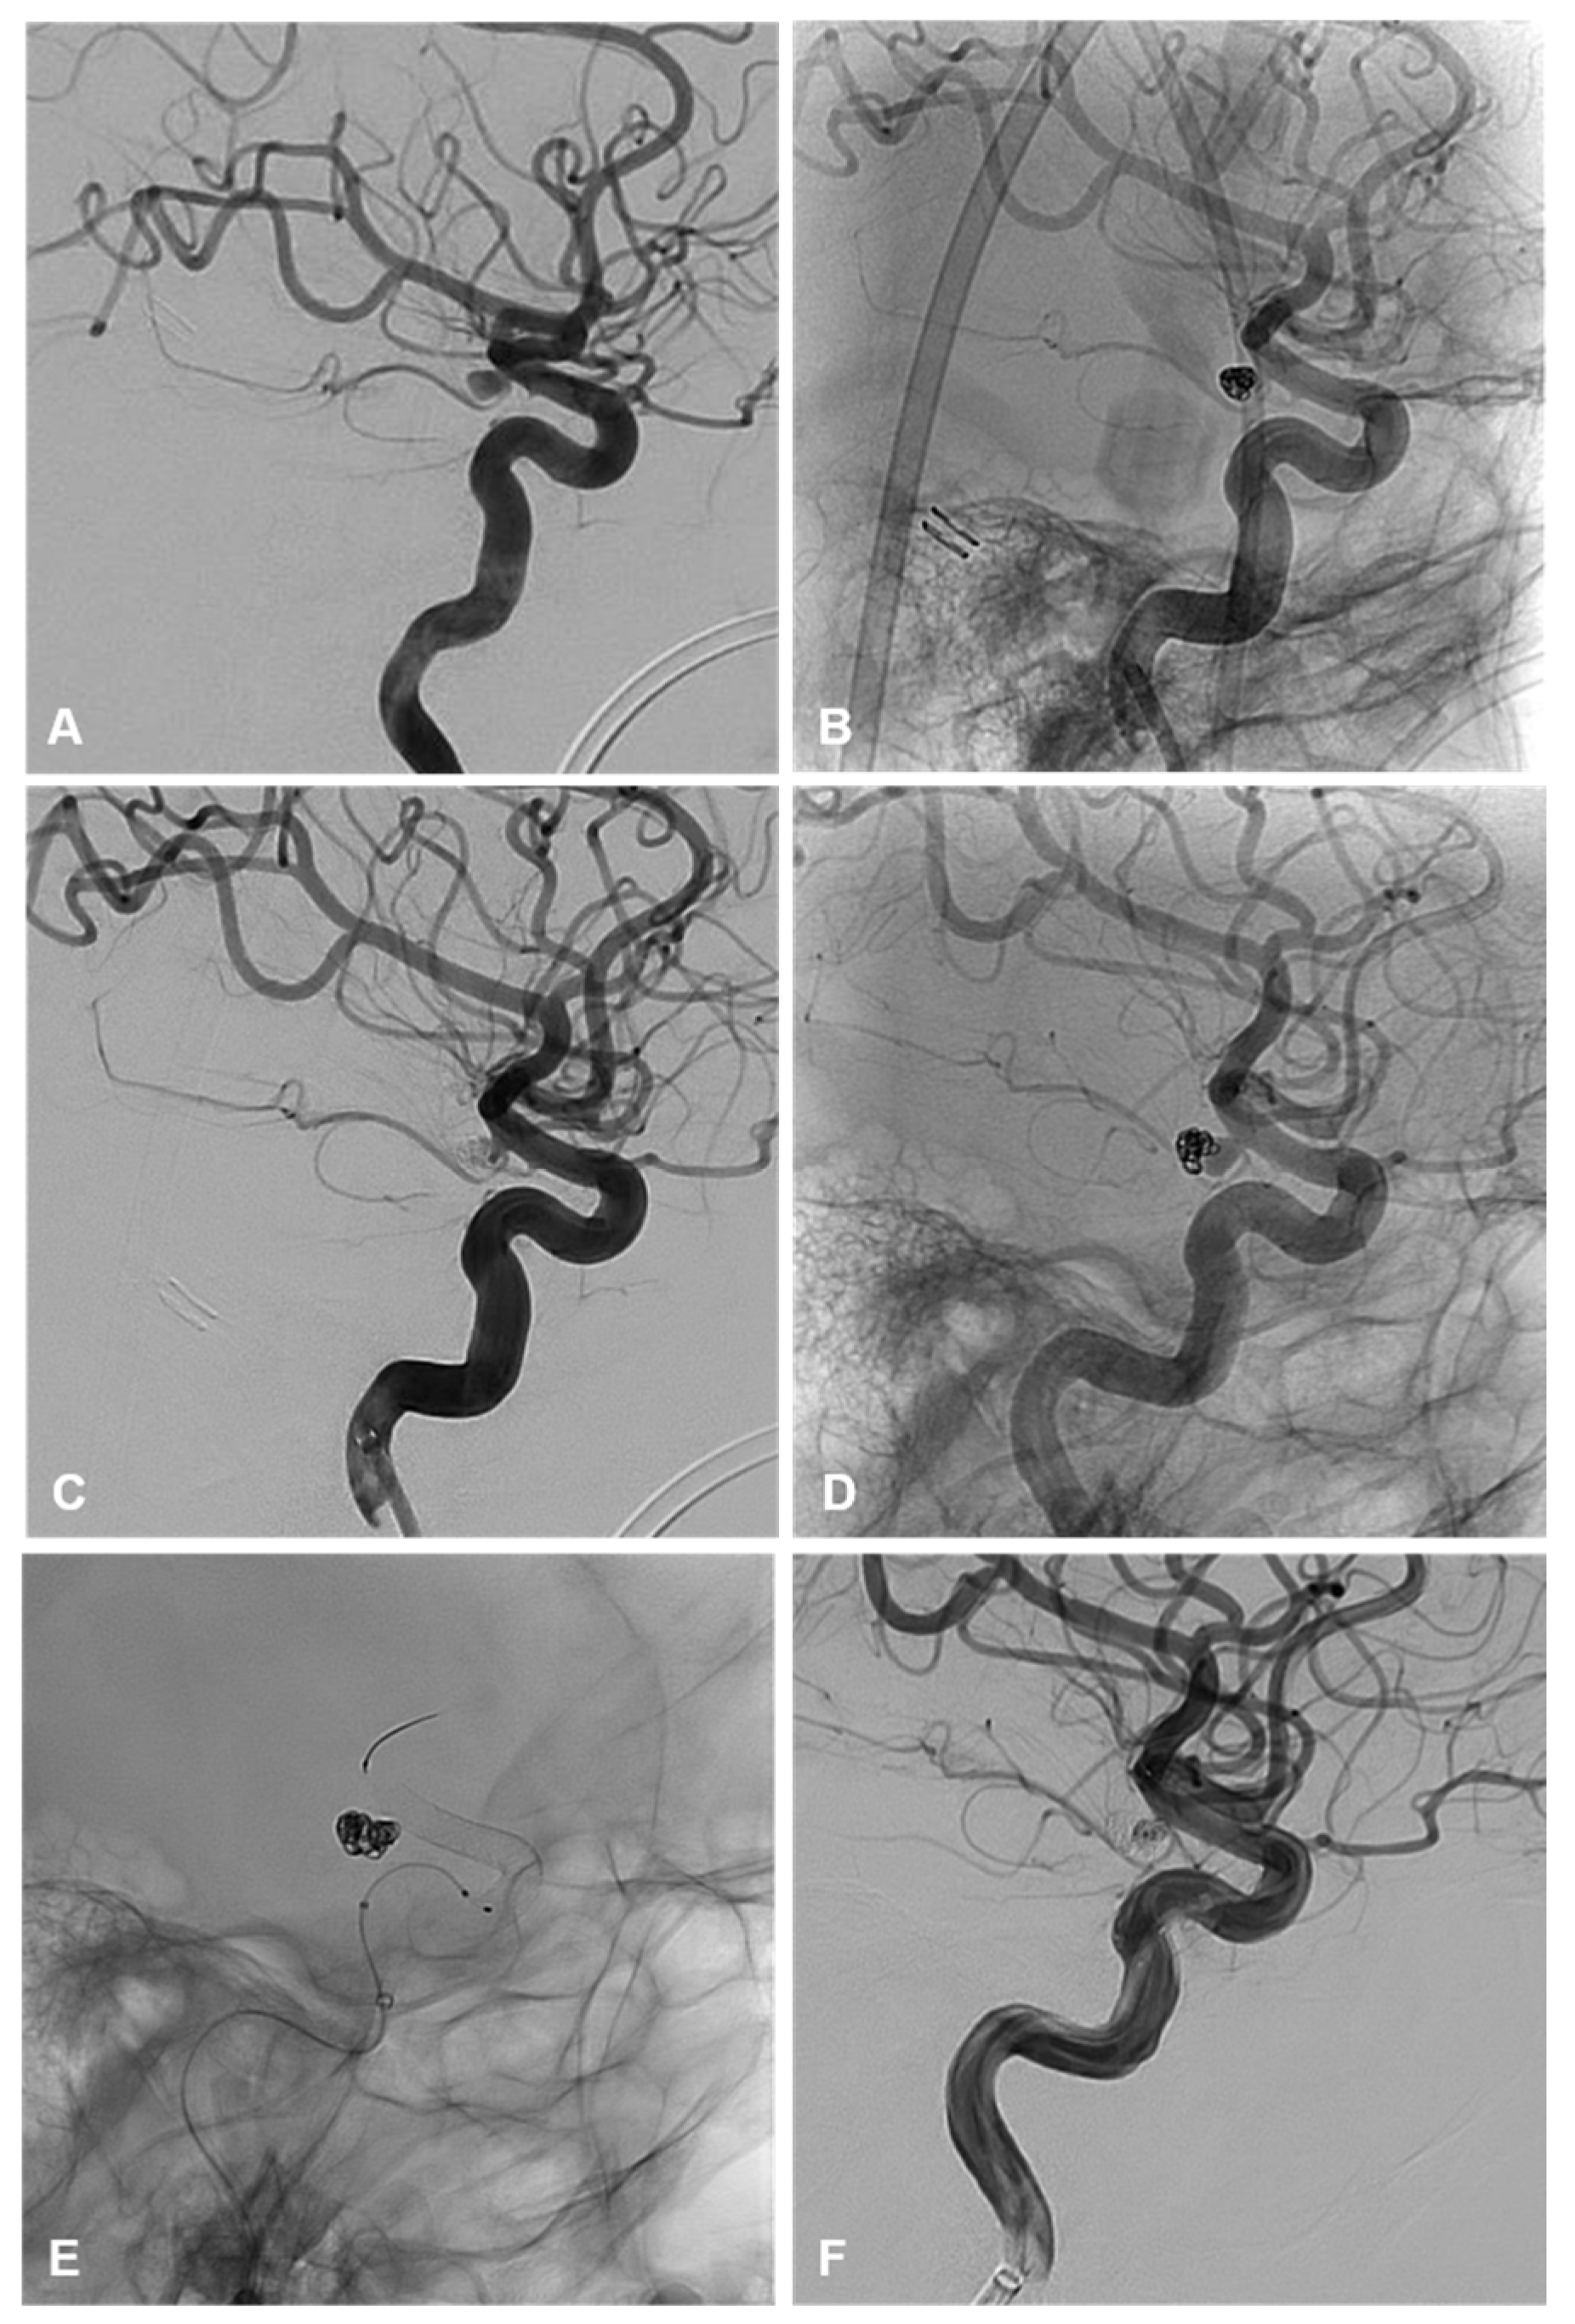

3.4.2. Recurrence and Retreatment

A total of 6/31 patients (19%) were retreated while 25/31 (81%) did not have a recurrence or need retreatment. Within the endovascular cohort, 3/24 (12.5%) patients required retreatment and 21/24 (87.5%) did not require any further treatment on follow-up (Table 3). Of those requiring retreatment, 2/3 (66%) were ruptured on initial treatment (Figure 1). One patient was initially treated with primary coiling and retreated by flow diverter stent, following recurrence after 5 months. The second patient was initially treated with primary coiling and was retreated with clipping due to recurrence after 3 months. Of these, 1/3 (33%) were unruptured on initial treatment with primary coiling and were retreated with a flow diverting stent (Figure 3).

Figure 3. (AC) demonstrate lateral angiographic images from the initial treatment of an unruptured AChoA aneurysm with primary coiling. (A) demonstrates a 4 mm smooth and saccular AChoA aneurysm that incorporates the origin of the AChoA at its neck. (B,C) are the unsubtracted and subtracted images of the final coil mass demonstrating a mRRC II and patency of the AChoA. (DF) demonstrate the lateral angiographic images of the second treatment with coiling and flow diversion following recurrence. (D) is the unsubtracted image demonstrating coil compaction with an enlarged neck residuum prior to retreatment. (E) demonstrates the unsubtracted image of the final coil mass and flow diverter. (F) demonstrates the final subtracted angiographic run post re-treatment with coiling and flow diversion with preserved patency of the AChoA and some filling of the coil interstices. Follow up MRA at 3 months demonstrated complete occlusion of the aneurysm.